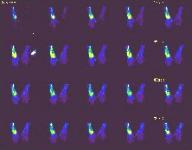

IMAGING FINDINGS:  A triple-phase bone scan was obtained on AIC's dual-head nuclear camera.  Fig. 1a-c show the angiographic (flow) images, blood pool images, and delayed (static) images of the wrists, respectively.  They demonstrate marked increased uptake in the left wrist in all 3 phases of the study.  Fig. 2a-b are selective pre and post-contrast MRI images of the left wrist showing precontrast T1-weighted (Fig. 1a) and postcontrast T1-weighted with Fat SAT (Fig. 1b).  They demonstrate diffuse edema in the marrow of all the carpal bones and proximal metacarpal bones with diffuse enhancement of the marrow and surrounding synovium.  X-rays (not shown) revealed diffuse osteopenia and erosions of the carpal bones.

DIFFERENTIAL DIAGNOSIS:  The bone scan findings are usually seen with osteomyelitis, but diffuse carpal involvement is unusual.  Increased uptake on all 3 phases can also be seen with Reflex Sympathetic Dystrophy (RSD) or an inflammatory process.  The MRI and x-ray findings are more compatible with an inflammatory process, particularly rheumatoid arthritis, with diffuse synovitis and erosions and reactive marrow changes, although this is a late presentation for the patient's age.